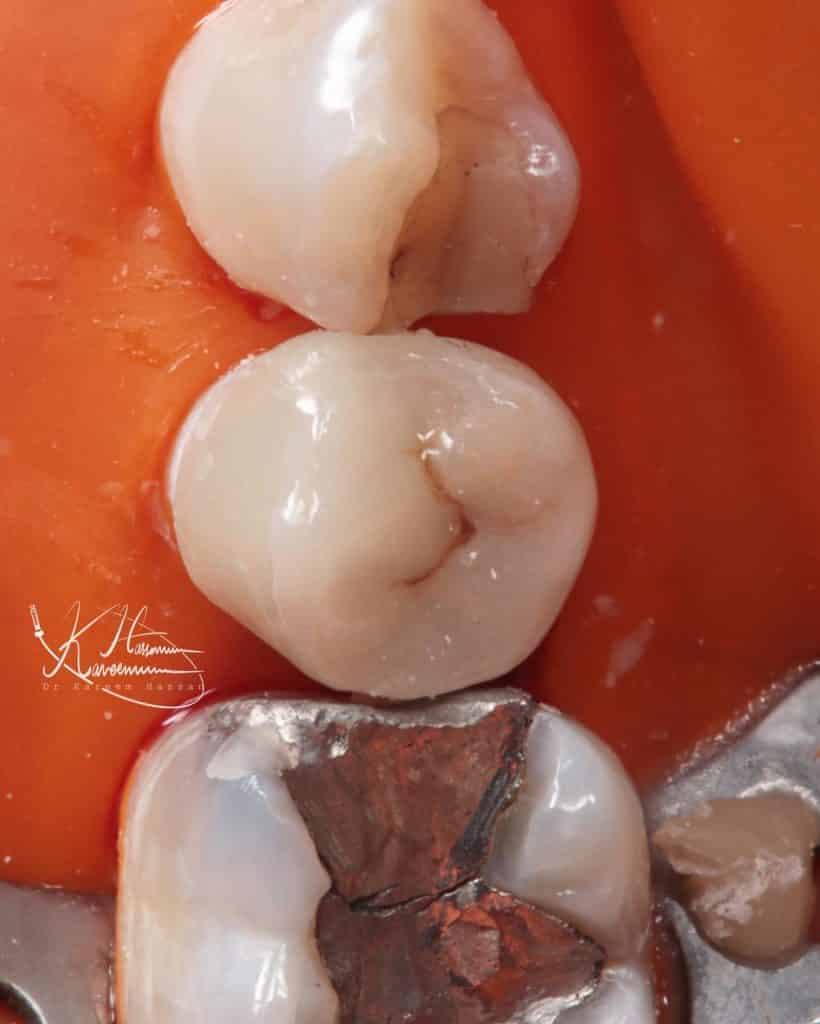

Initial situation

After caries remove with CDD , and create Biobase

Emax from pink lab